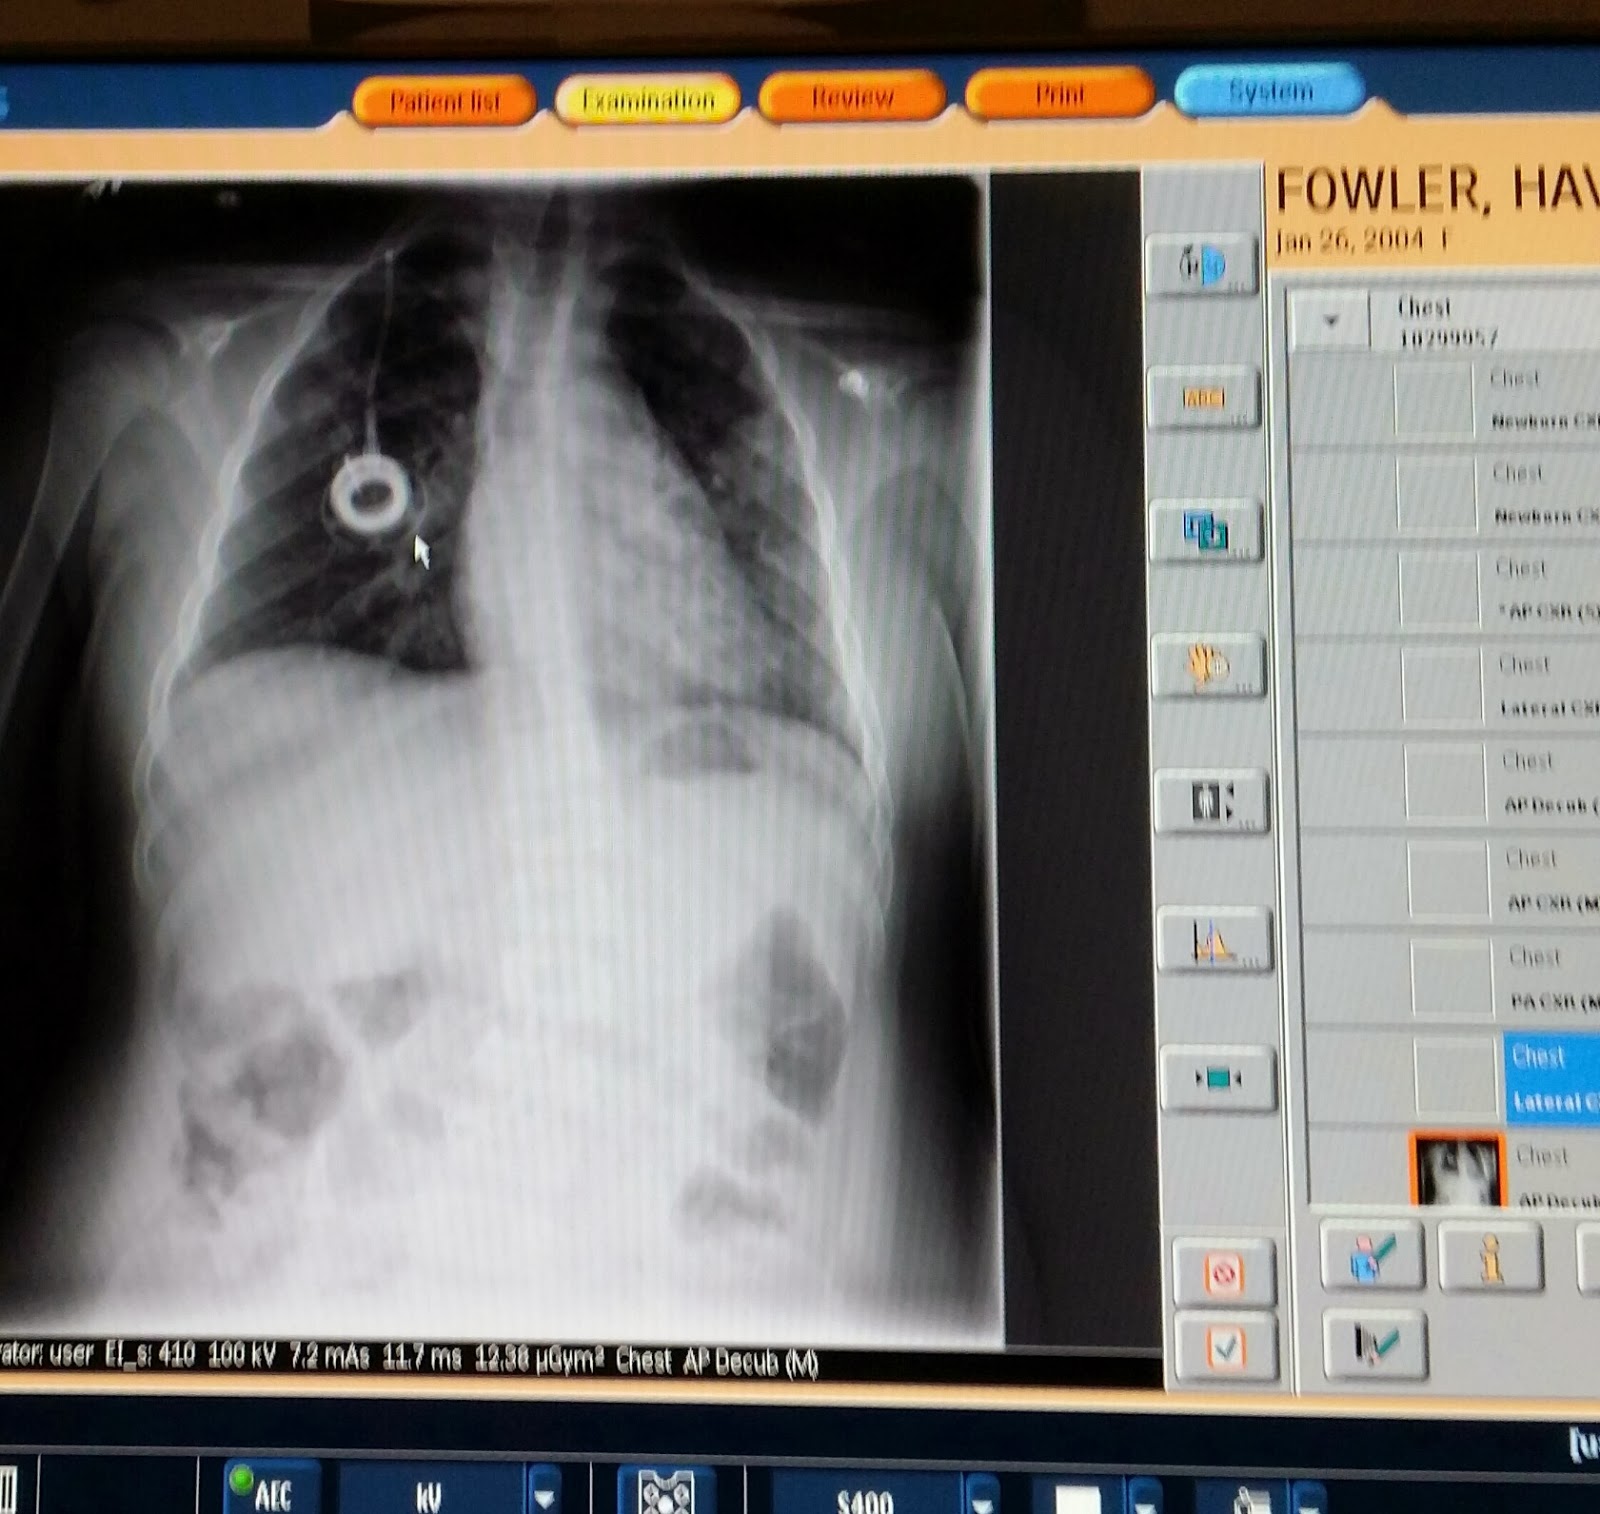

Her doctors here are able to contact her doctors at Hopkins and actually work very close with her old Pulmonary doctor from Hopkins as he travels here every few months and will be here again this summer. They were able to view her last report from October 2011 which showed she only had evidence of sleep apnea with a Respiratory Disturbance Index (RDI) of 4.6 events per hour. On December 2013 (2 years later) she showed Severe Obstructive Sleep Apnea with a RDI of 30.8 events per hour.